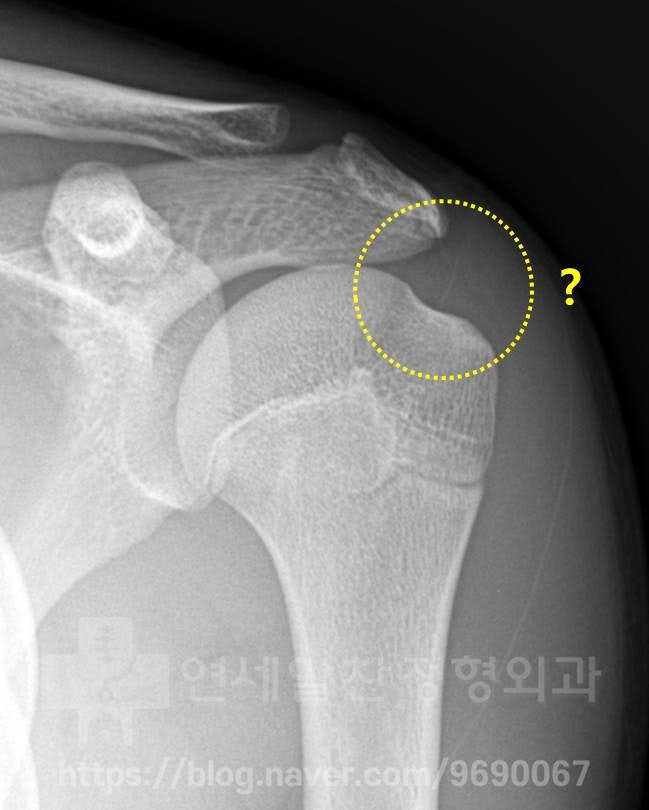

X-ray 사진에서 보았을때 전혀 문제 없는 정상적인 소견이 관찰되었습니다.

X-ray 상에서는 정상적인 소견이 관찰됩니다.